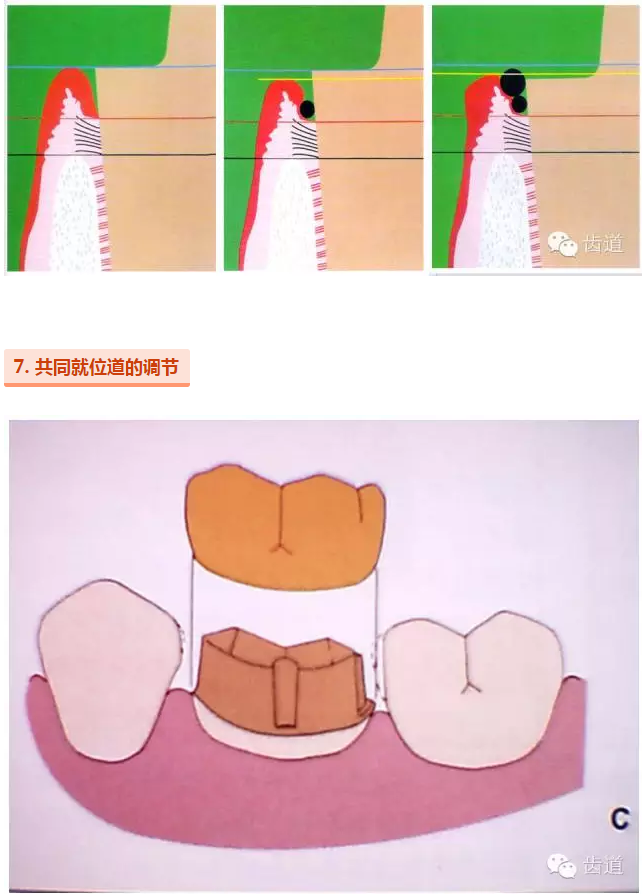

l保護牙周組織

l多個基牙時就位道的調(diào)節(jié)